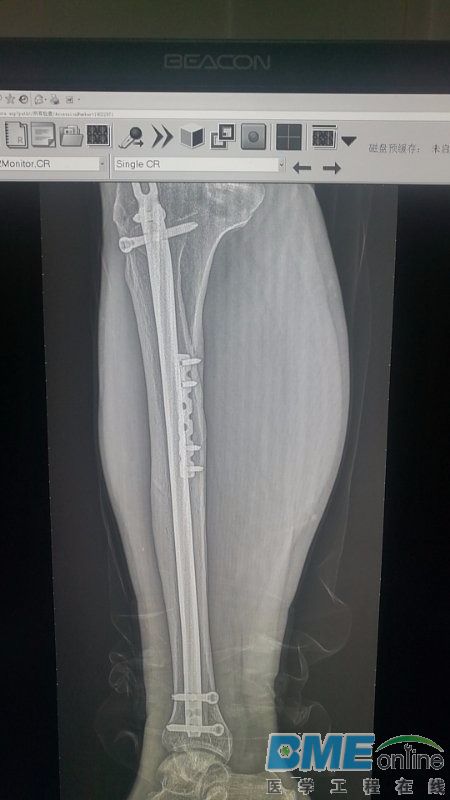

图像有珊纹

这条腿看着吓人啊

请教一下各位,佳能DR拍片有竖纹 求指点

不是珊纹

平板已经校正